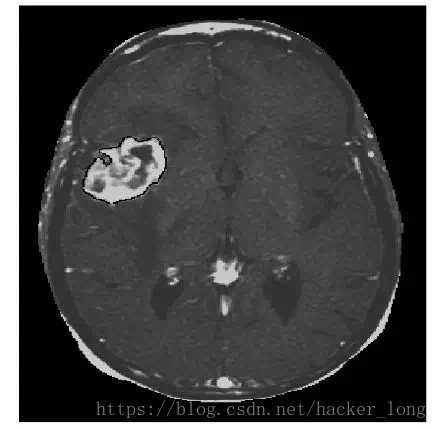

下面是我的硕士论文【6】中采用水平集方法分割出的肿瘤,就是白色那一块。这个方法的数学味有点浓,考虑到咱们是闲聊,就不摆公式了,毕竟后面还有很多事。